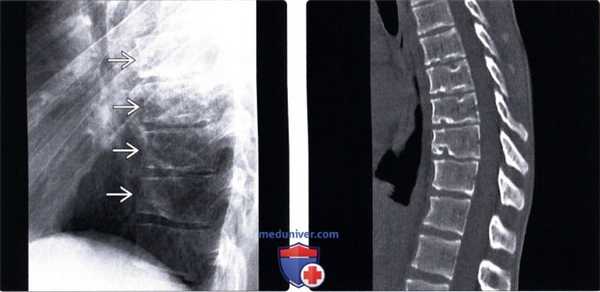

2. Рентгенологические данные:

• Рентгенография:

о ≥ трех соседних позвонков, клиновидная деформация тела каждого из которых > 5°

о Волнообразная деформация замыкательных пластинок на фоне множественных инвагинаций межпозвонковых дисков

о Снижение высоты межтеловых пространств, наиболее выраженное в переднем отделе о Четко ограниченные грыжи Шморля

3. КТ при болезни Шейерманна:

• Костная КТ:

о Более явно видны изменения замыкательных пластинок

(Слева) Рентгенограмма в боковой проекции: неровность замы-кательных пластинок и клиновидная деформация тел позвонков. Вдавления замыкательных пластинок придают им волноообразный вид, что отличает их от остроугольных вдавлений, наблюдаемых при переломах.

(Справа) КТ, сагиттальный срез: многоуровневое изменение замыкательных пластинок и клиновидная деформация тел позвонков. Диагностические критерии болезни Шейерманна включают поражение по меньшей мере трех соседних позвонков (грыжи Шморля) и клиновидную деформацию каждого из измененных позвонков по меньшей мере 5°, что и имеет место в данном случае.